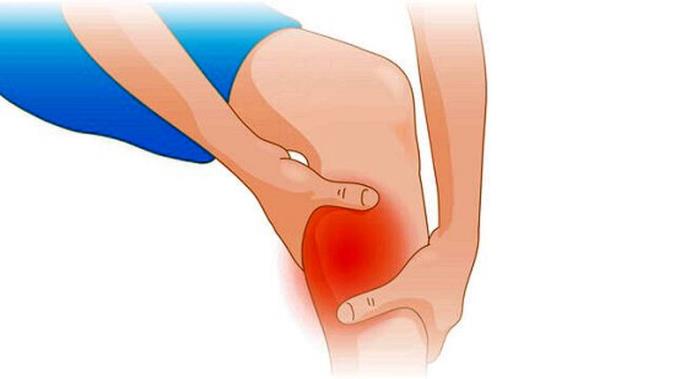

گرفتگی عضلات زمانی رخ می دهد که بطور ناگهانی یک و یا چند عضله شما دچار انقباض و کشیدگی می شود.اگر تاحالا بطور ناگهانی هنگام دویدن و یا در خواب دچار گرفتگی عضلات، شده باشید، پس می دانید که چقدر دردناک و آزاردهنده است.

هرچند عموما گرفتگی عضلات خطرناک نیست، اما درد آن آزاردهنده می باشد و می تواند بطورموقت استفاده از ماهیچه را غیرممکن نماید.

بعلاوه گرفتگی عضلات پا و ساق پا، سایر ناهیچه ها همچون ماهیچه های کمر، دست ها، شکم و … نیز دچار گرفتگی می شوند.

علائم اصلی اسپاسم عضلات بسته به محل آسیب یا بیماری زمینهای معمولاً شامل کمر درد حاد یا درد گردن بوده، که همراه با احساس سفت شدن شدید عضله که ممکن است در دورههایی از چند ثانیه تا چند دقیقه رخ دهند، میباشد.درد و سختی در واقع با دو منظور ایجاد میشود: برای اعلام وجود یک مشکل و برای محافظت از بافت و ساختارهای متاثر در مقابل آسیب بیشتر از طریق محدود کردن حرکت. علائم غالباً پس از یک فعالیت فیزیکی بصورت ناگهانی ظاهر شده و معمولاً پس از یک دورهی استراحت آرام میشوند.